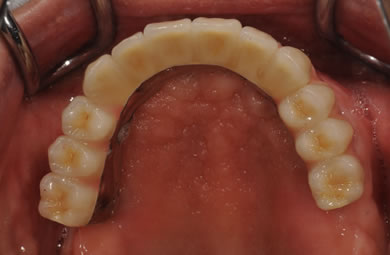

インプラントの症例写真 IMPLANT

骨再生スピードインプラント治療+AGC連結セラミック治療

| 治療内容 | インプラント12本(サイナスリフト+GBR+抜歯即日スピードインプラント+遊離歯肉移植)、AGCハイブリッドセラミック連結ブリッジ2装置(上顎・下顎)、テンポラリーインプラント2本 | ||||||||||||||||||||||||||||||||